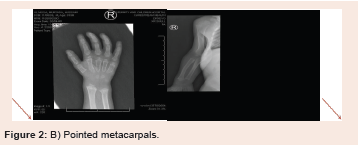

On Skeletal Survey, the radiological finding fitting the definition

of (dysostosis multiplex) including central anterior vertebral body

breaking involving most of the visualized thoraco-lumbar vertebrae

associated with appearance of flared iliac wings, metaphyseal flaring

of the femoral and tibial bones as well as proximal pointing of the

metacarpal bones. There is isolated partial agenesis/hypogenesis

of the 5th sacral vertebra. Snoring was infrequent complaint

infancy or sometimes later in childhood (Figure 2).